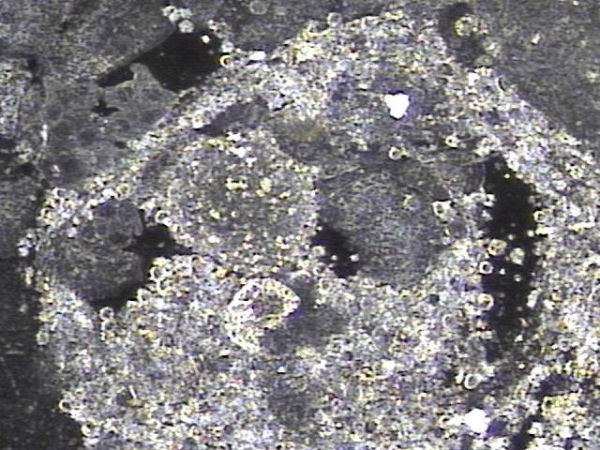

첫 내원일후 한달 보름 주 2~3회 전립선의 표적 치료후 사정관과 정낭 그리고 사정관입구에 막혀 있던 탈락된 상피 세포가 치료된 현미경학적 자료입니다.

This is a microscopic image showing the improvement after 6 weeks of targeted prostate treatment, performed 2 to 3 times a week. The treatment helped clear away the accumulated, shed epithelial cells that had been blocking the ejaculatory ducts, seminal vesicles, and the opening of the ejaculatory ducts.